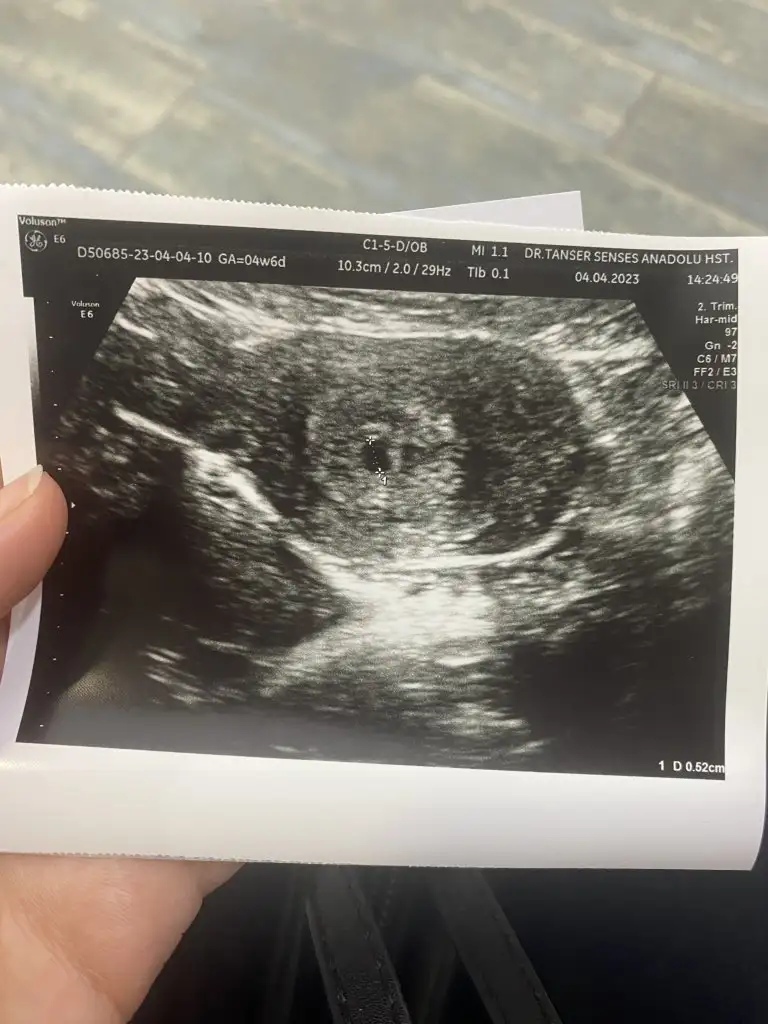

6.2mm yazıyor canım, hayırlısıyla kucağına almayı nasip etsin Allahım 🙏🏼 bende bir kaç saate gidicem inşallah benimde kese gözükür 😊

canım sağolasın. inşaallah sende görürsün bugün :) insan bir nebze rahatlıyor, sonra hemen kalp atışı duyacak mıyım diye endişe başlıyor allah yardımcımız olsun :)